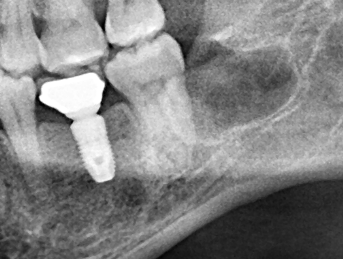

☆本院特別巨資增設 ”千萬級3D AI透視電腦斷層”,並配合“成骨膠原蛋白”施作 (上述兩項目前健保無給付),讓您遠離神經傷害、口鼻竇(炎)相通...等併發症,除健保之外,難免會有避免併發症風險的自費項目,網路上經常會有看到智齒拔完後唇麻、舌麻、口鼻竇相通等併發症,在本院嚴格自我要求下,此類併發症在本院幾乎趨近於零。

外面一顆要拔兩個小時,本院一顆十分鐘

外面拔完時常術後唇麻舌麻,本院發生趨近於零

外面拔時易斷裂於骨頭內而難以取出